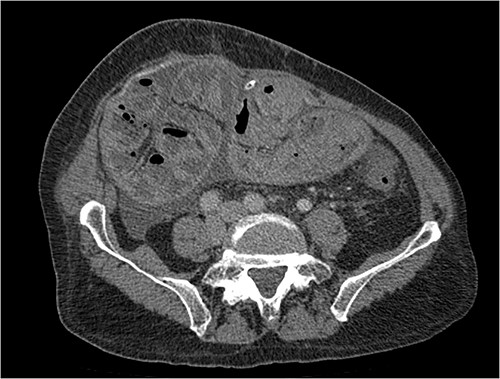

His clinical history and contrast-enhanced computed tomography (CT) findings (Figs 1–3) were compatible with EPS in Stage 4 (Table 2). Laboratory tests were non-specific, showing inflammation and malnutrition. He underwent nutritional support, corticosteroids and surgery. In surgery, fibrocollagenous membrane resection and enterolysis were done. Postoperative period was complicated by pneumonia treated with piperacillin+tazobactam and later bacterial peritonitis treated with ertapenem. The patient was discharged after 29 days with adequate nutrition and asymptomatic.

Portal phase transversal section image on CT showing membrane-like structure and loculated ascites (asterisk).

Imaging exams, mainly CT are important to evaluate causes of bowel obstruction [4]. Dilated or non-dilated small intestine loops may be wrapped in a membrane-like structure, proximal bowel dilatation, thickened peritoneum with diffuse or local calcification, and loculated ascites are some of the findings on CT [1, 12]. Barium X-ray provides a clue to bowel encapsulation, showing clustered loops of the small intestine in the center of the abdomen, known as the cauliflower sign [4]. Ultrasound and magnetic resonance imaging may give a clue but are rarely used [1, 12].